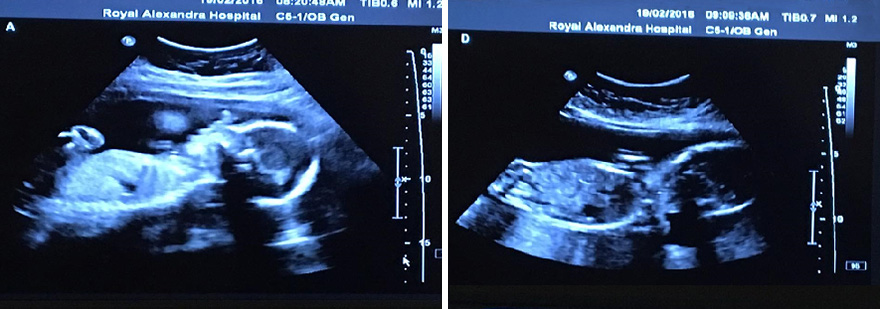

The chances of having spontaneous quadruplets (non-assisted) are predicted to be one in 729,000. As you could imagine, having identical siblings is even rarer. One lucky Canadian couple, Bethani and Tim Webb, beat the odds of one in 15 million and, on May 6th, 2016, gave birth to 4 identical baby girls – Abigail, Mckayla, Grace, and Emily. Now, two months later, the sisters have starred in an adorable nature-themed photo shoot and it’s making our hearts melt.